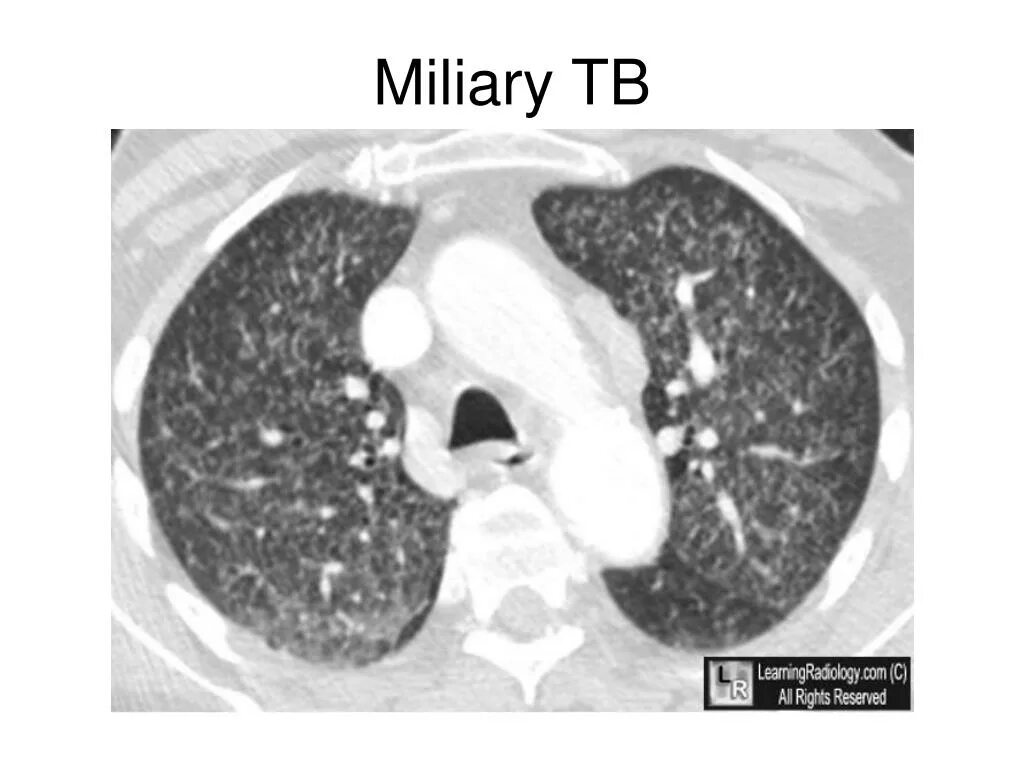

Туберкулез горла